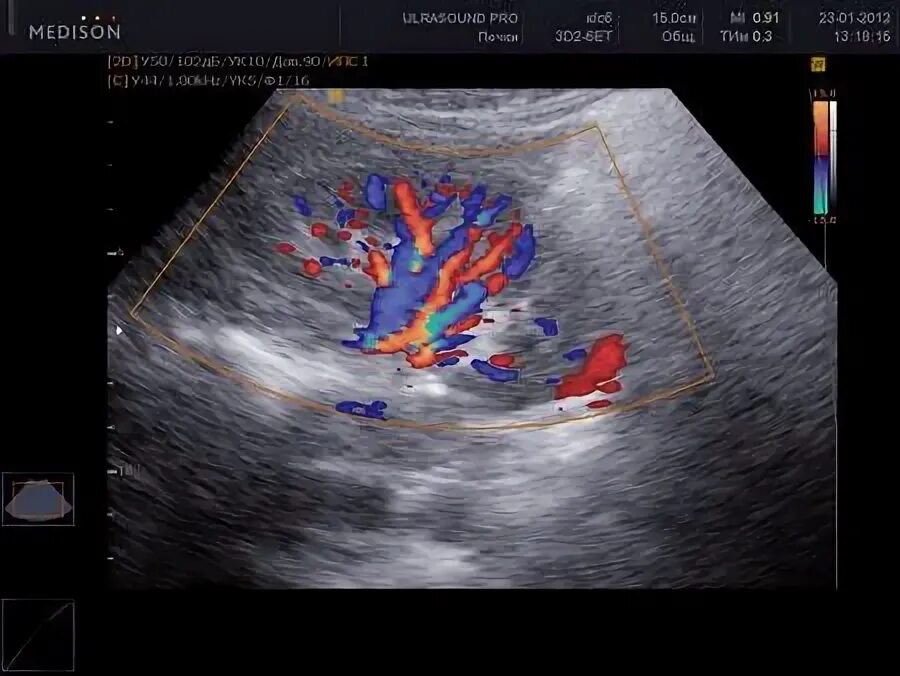

Локусы при цдк что это